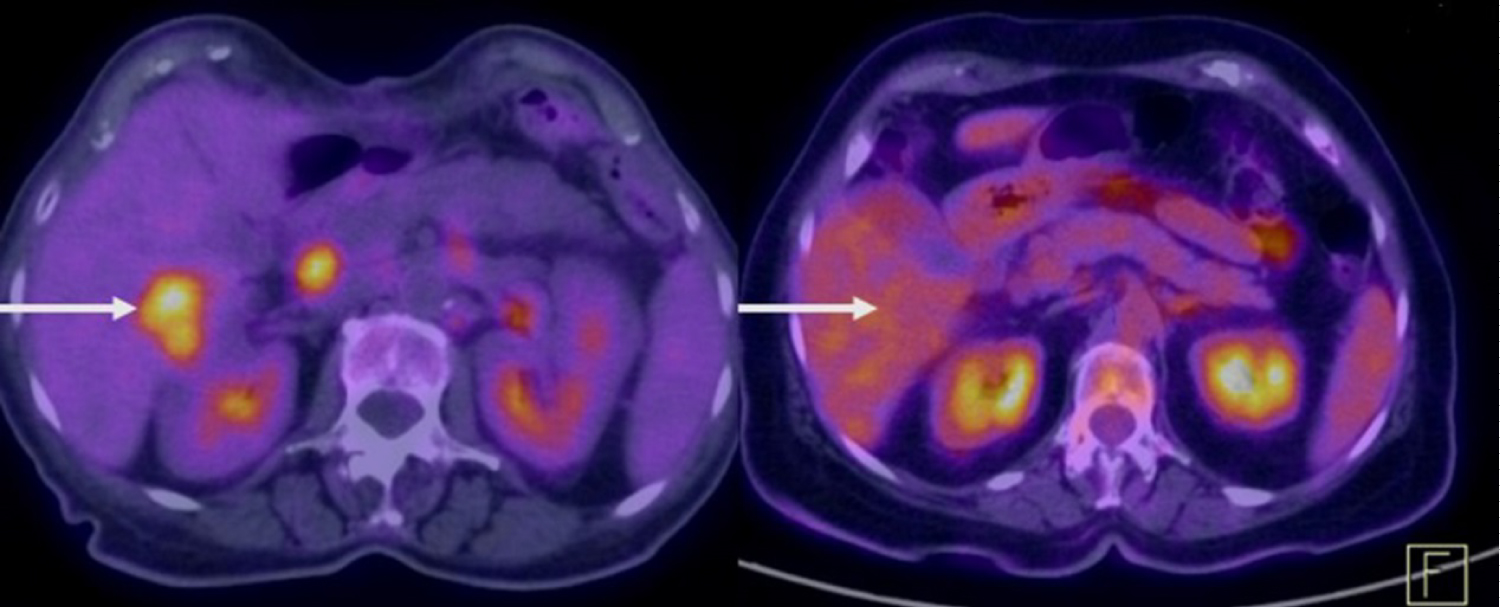

A 72-year-old woman in June 2015 was diagnosed with AJEG G2 (Figure 1 and Figure 2). The oncologist suggested a neoadjuvant chemotherapy scheme with Capecitabine, Oxaliplatin, and Epirubicin (EOX). However, this was not approved because of the cardiotoxicity of Epirubicin since the patient had coronary artery disease and a stent installed. Therefore, neoadjuvant chemotherapy was administered with only Capecitabine plus Oxaliplatin. Unfortunately, she had a severe infusion reaction with edema of the glottis during the second application of Oxaliplatin, preventing its further use. This was then followed by therapy with Capecitabine alone, because of which the patient developed extensive gastrointestinal toxicity requiring prolonged hospitalization, experienced significant weight loss (20 kg in 33 days) and underwent a gastrostomy. We chose to stop the neoadjuvant chemotherapy, and during the months of recovery, she had progression of local disease. In November 2015, the patient underwent gastroesophagectomy (total esophagectomy with extensive gastrectomy and creation of a neoesophagus with great gastric curvature) with an uneventful postoperative period. She had six months without any cancer treatment. In May 2016, a positron-emission tomography and computed tomography (PET-CT) performed on the patient identified nodal, liver, and peritoneal progression and prompted an examination with Personna® Onco, a genetic analysis tool that uses sequencing technology for analysis of multigenic next-generation sequencing (NGS). This examination discarded HER-2 changes and identified the PI3Kca mutation.

Figure 1: Upper Gastrointestinal Endoscopy showing deep ulceration in the gastric esophagus transition (arrow) and in rear view shows the folds (arrowheads). View Figure 1

In June 2016, a new weekly chemotherapy regimen with Paclitaxel was begun. After 3 cycles, a PET-CT performed in January 2017 to evaluate response to treatment, found increased lymph nodes and liver subcapsular nodules in segment VI, suggesting progressing disease (PD) compared to the PET-CT in September 2016. Treatment with isolated Ramucirumab was started. In March 2017, Magnetic Resonance Imaging (MRI) showed progressive worsening nodal and liver PD (Figure 3 and Figure 4). Without the expected response to Ramucirumab, in May 2017, we changed the treatment line to Irinotecan alone. A PET-CT performed in June 2017 showed a favorable tumor response; however, partial treatment was instituted (dimensions of increased peritoneal thickening in iliac fossa were related to the increase in necrotic component and not to disease progression). Once isolated, the patient continued Irinotecan for 10 biweekly applications. In September 2017, an MRI revealed a liver nodule in the caudal aspect of segment IV with hypermetabolism signals, infectious and inflammatory changes involving the gallbladder and the liver parenchyma, and increased volume of the right ovary, which had a heterogeneous appearance. After 10 days, ultrasonography showed signs of cholecystitis and compression of the cystic duct by the hepatic hilum lymph node. During this period, the patient underwent microsatellite instability testing noting high instability (favorably to treatment with immunotherapy - being suggested for Pembrolizumab use). However, because immunotherapy treatment can only be initiated in the absence of inflammatory processes, a cholecystectomy was required. While awaiting surgery, the patient developed jaundice. Therefore, prosthesis installation was required in the common bile duct by Endoscopic Retrograde Cholangiopancreatography (ERCP), and during the procedure, we opted for permanent metal prosthesis. In September 2017, the patient underwent a cholecystectomy.

Figure 4: PET-CT in 2017 demonstrating liver nodular lesion in a study carried out immediately before the use of Pembrolizumab suggestive of a secondary implant and in the left at the same level, no longer showing the lesion after using Pembrolizumab, suggestive of complete regression in 2018. View Figure 4

In October 2017, after an uneventful postoperative period, the first cycle of immunotherapy was administered with Pembrolizumab 200 mg every 3 weeks. The patient remained in this regimen until revaluation in February 2018 without any relevant side effects. A PET-CT performed in February 2018 demonstrated a set of evolutionary findings suggesting favorable tumor response to treatment. A comparative analysis with the previous PET-CT in September 2017 had not more showed/shown lymphadenopathy in the porto-caval region and not revealed a significant increase of the radiotracer in peritoneal findings and a decrease in attenuation coefficients, suggesting a predominance of the necrotic component (adnexal right, just a capsular in liver segment VI, the hepatic hilum, the mesentery at the level of the right iliac fossa, left pre-sacral, and sigmoid handle inseparable). Thus, it was established that there was a favorable response by the drug.

Due to an excellent therapeutic response, the patient was maintained on Pembrolizumab every 3 weeks for another 4 months. A PET-CT in July 2018 not showed the small nodular lesion in liver segment VIII on a comparative analysis with the study from February 2018 and continues ever since (Figure 4).